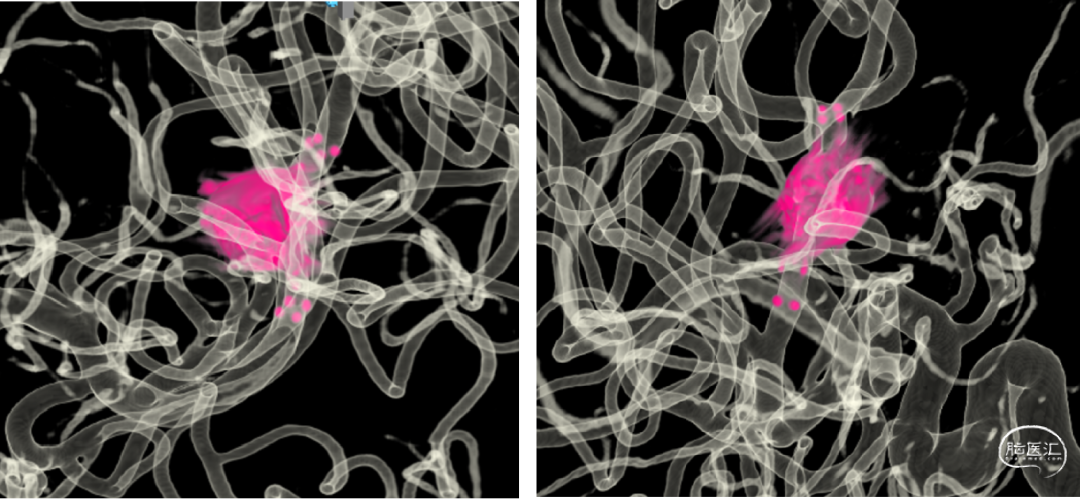

外院CTA:左侧大脑中动脉M1、M2段动脉瘤

AI风险评估

手术规划:FD+弹簧圈

FRED 3.0x14/19